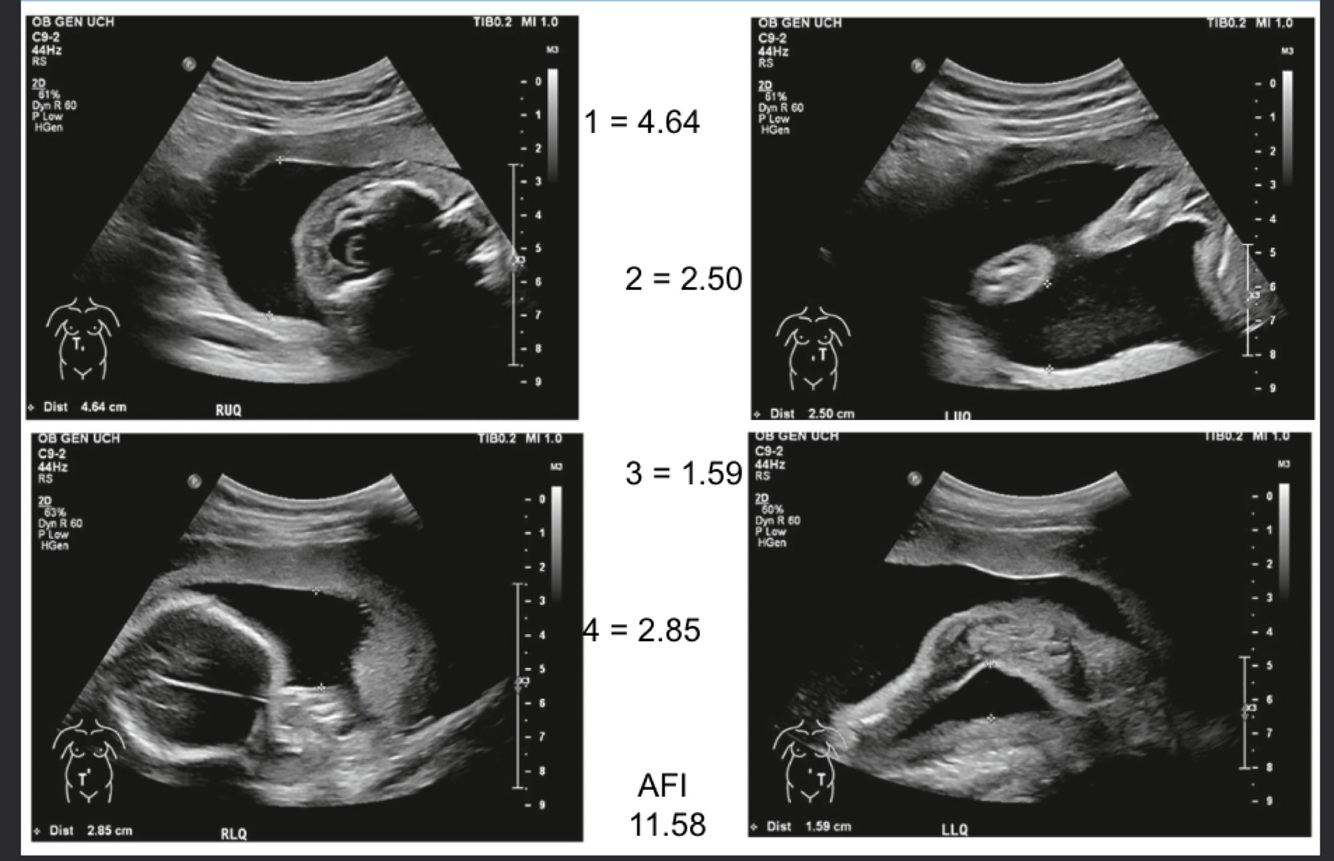

Q

What does this image demonstrate?

A

AFI measurements in the four quadrants

Polyhydramnios, AFI is >25cm